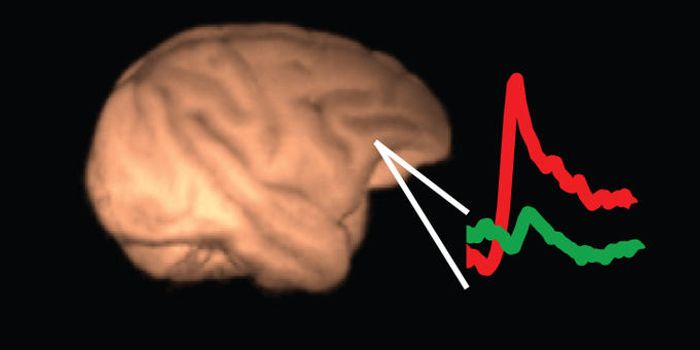

JUN 30, 2016NeuroscienceWhen there has been a traumatic brain injury (TBI) or there is a tumor or other problem in the brain, doctors need to kn ...

JUN 07, 2016NeuroscienceA traumatic brain injuries, or TBI, can be devastating and have long-lasting effects. In children these injuries can be ...

MAY 04, 2016NeuroscienceRupture of small blood vessels in the brain can cause hemorrhagic stroke and brain microbleeds, and finding the fastest ...

JAN 28, 2016NeuroscienceWhen a patient suffers a stroke, the key factor is time. Neurologists call it a Golden Window where “time is brain ...